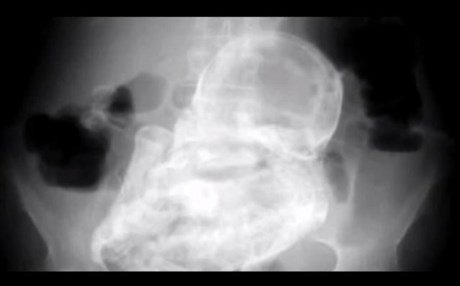

Αρχικά οι γιατροί διέγνωσαν γαστρεντερίτιδα όμως παρά τη θεραπεία οι πόνοι δεν υποχωρούσαν. Μια ακτινογραφία έδειξε το εκπληκτικό φαινόμενο: ένα απολιθωμένο έμβρυο μέσα στην κοιλιά της ηλικιωμένης γυναίκας!

Το έμβρυο είχε απολιθωθεί πλήρως με τα χρόνια όμως ο νεκρός ιστός που το κάλυψε, το συγκράτησε στην κοιλιά της γυναίκας.

Το σπάνιο φαινόμενο ονομάζεται λιθοπαίδιον (lithopedion η επιστημονική ονομασία) και υπολογίζεται ότι μπορεί να συμβεί σε μια κάθε εκατομμύρια κυήσεις. Συμβαίνει όταν ένα γονιμοποιημένο ωάριο προσκολλάται σε ιστούς και αναπτύσσεται έξω από τη μήτρα, συνήθως στις σάλπιγγες. Μπορεί όμως αν αποκολληθεί από εκεί προτού η γυναίκα καταλάβει την κύηση να μεταφερθεί σε κάποιο άλλο σημείο της κοιλιακής κοιλότητας. Δεν μπορεί βεβαίως να αναπτυχθεί αλλά μπορεί να παραμείνει στο σώμα της γυναίκας. Δεν μπορεί να αναπτυχθεί αλλά ο οργανισμός της γυναίκας το καλύπτει με ιστό προκειμένου να μην αποτελέσει αιτία μόλυνσης.